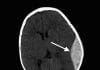

NEXUS II kriterleri, kafa travması geçiren hastalarda beyin BT (bilgisayarlı tomografi) çekilmesi gerekliliğini belirlemek için geliştirilmiş klinik karar kurallarıdır.

NEXUS II kriterlerine göre, aşağıdaki bulgulardan en az birinin bulunması durumunda beyin BT çekilmesi endikedir:

- Açık kafa yaralanması veya kafa tasında görülen kırık bulgusu